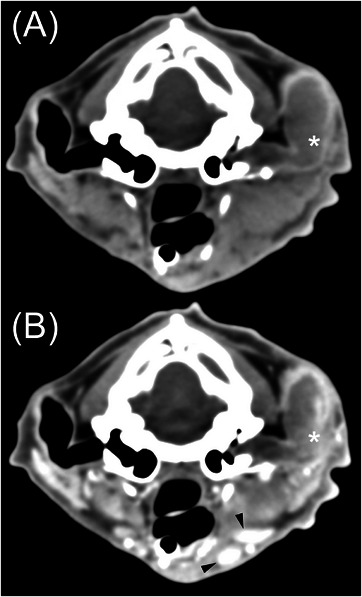

Computed tomography is commonly used to evaluate feline otic disease; however, published studies characterizing the CT appearance of ear canal neoplasia are limited. The purpose of this multicenter, retrospective, secondary analysis, cross-sectional study was to describe the CT features of histopathologically confirmed feline ear canal neoplasia. The CT studies of 25 cats with ear canal neoplasia were prospectively scored by consensus of two veterinary radiologists. Recorded parameters were the presence of focal or multifocal tissue enlargement (mass/masses), lesion shape, location of the center of mass, attenuation characteristics, features of contrast enhancement, involvement of otic structures, calvarial and brain changes, changes of nearby structures, and lymphadenopathy. There was a significant overlap of CT findings between cats with malignant ceruminous gland neoplasia, ceruminous gland adenoma, and squamous cell carcinoma (SCC). Ceruminous gland adenoma was typically homogeneous in attenuation with homogeneous contrast enhancement and no intralesional fluid accumulations (IFAs) or involvement of adjacent structures. In contrast, SCC consistently had heterogeneous attenuation, heterogeneous contrast enhancement, IFAs, and involvement/invasion of adjacent structures. Malignant ceruminous gland neoplasia had variable attenuation and pattern of contrast enhancement with occasional IFAs and occasional involvement/invasion of adjacent structures. Knowledge of these imaging features will inform the creation of prioritized differential diagnosis lists. However, a biopsy is required to confirm the diagnosis.